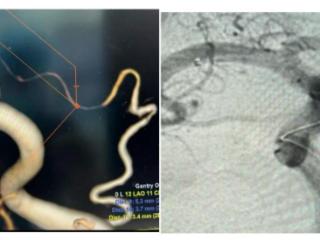

微创手术化解“脑内炸弹”,济南南郊医院脑科精准治愈颈内动脉瘤